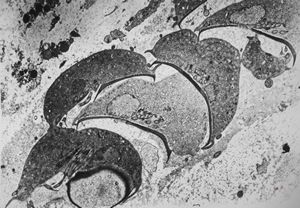

Giardia (Lamblia) intestinalis